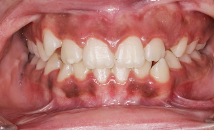

✅ 2. 잇몸이 붓고 붉은빛을 띤다

건강한 잇몸은 연한 분홍빛인데,

치은염이 있으면 잇몸이 붉게 변하고 부풀어 오른 느낌을 줍니다.

특히 치아 경계 부분이 뚜렷하게 부어 보이거나

미세한 통증·불편함을 동반할 수 있어요.